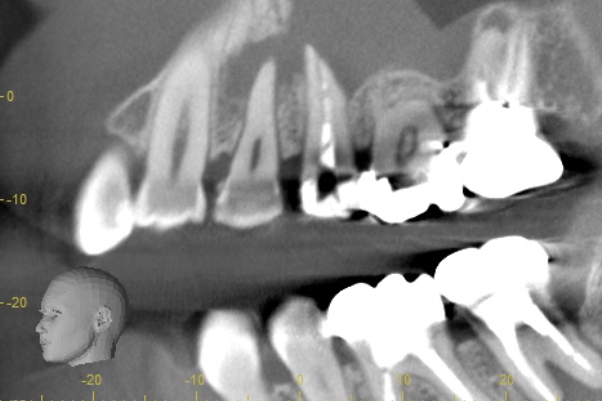

| 根の中にお薬を充填した後のCT画像。やはり根の先に黒い影があるのがわかります。 |

患歯を見極めるためと、状態の悪さをみるため、CTを撮影しました。治療前では上顎洞への大きな炎症が見られます。また、上顎洞底線も無くなっています。また左上の前から4番目の歯の根尖周囲にも透過像が見られます。5番目の歯に関しては根尖が鋭利になっており、根尖性歯周炎によって吸収されたことがわかります。ですので、まず第一の患歯は5番目の歯であるとしました。

治療後3ヶ月経つと上顎洞への炎症も無くなっています。また、上顎洞底線もきれいにみえます。4番目の歯の根尖周囲の透過像もなくなりました。5番目の根尖にまだ透過像がありますが、臨床的症状がないことから、治癒傾向にあるものと判断しました。